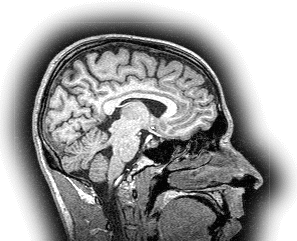

MRI